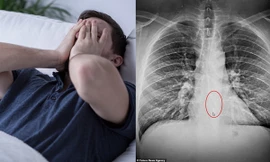

HHTO - Apple AirPods có kích thước khá nhỏ nên người dùng rất dễ thất lạc hoặc mất chúng. Tuy nhiên, một điều hy hữu đã xảy ra với Bradford Gauthier, một người đàn ông đến từ Massachusetts (Mỹ), khi người này làm thất lạc AirPods khi đeo tai nghe... trong lúc ngủ.